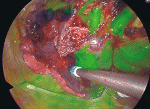

URATSは,単孔式手術専用のシステムを購入しなくても単孔式でロボット手術を行うことができる方法である.3Dの視野でより精密な操作ができるロボットシステムは立体的な区域間の同定が必要な区域切除に有用である.アーム間の干渉が問題になるが,干渉の少ない視野軸を探しながら手術を行う.URATSは左手の鉗子で組織を把持して手術を行うことが可能となるためより複雑な手技も可能になる.